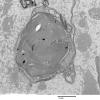

PERIPHERAL NEUROPATHY

4 Pi Granules (of Reich) (2)